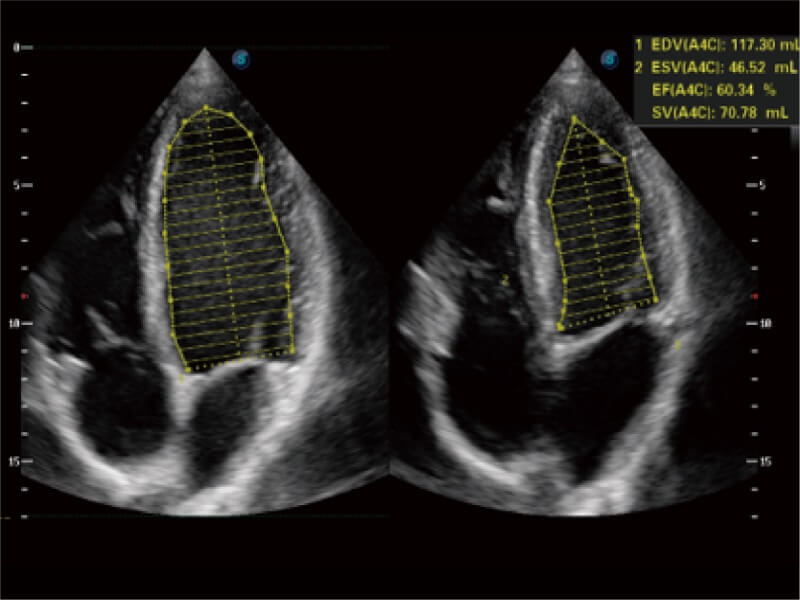

Auto EF spart gegenüber der manuellen Messung mehr Zeit und Mühe, da die Ejektionsfraktion anhand der linksventrikulären Wandbewegung und der Simpson-Regel berechnet wird.

Spart anhand der linksventrikulären Wandverfolgung und der Simpson-Regel gegenüber der manuellen Messung Zeit und Mühe.